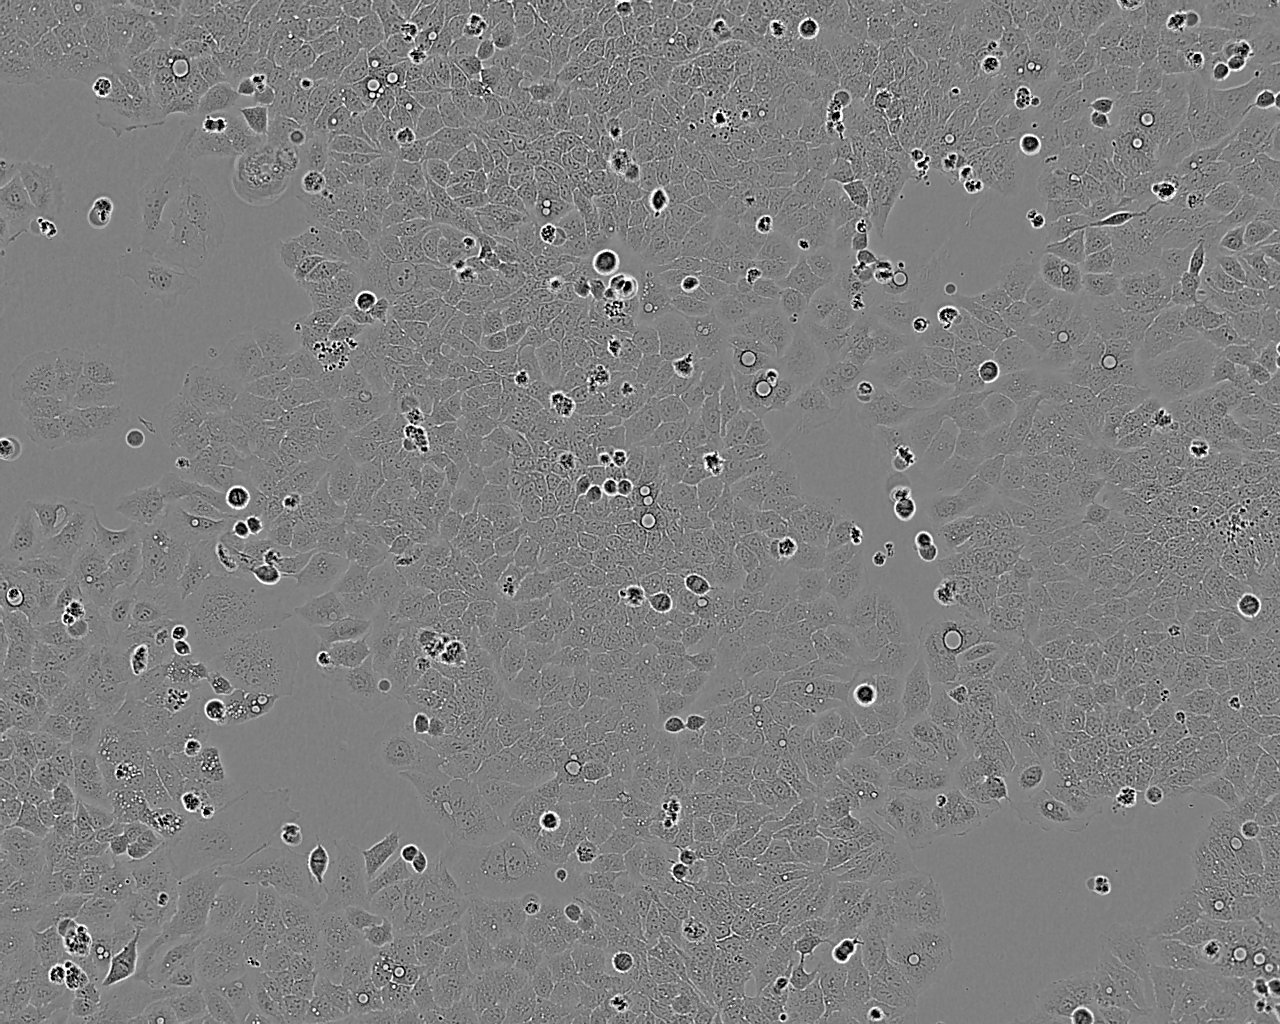

细胞形态:上皮细胞样

细胞生长:贴壁

细胞生长特性:悬浮生长,聚团

细胞形态特性:聚团悬浮